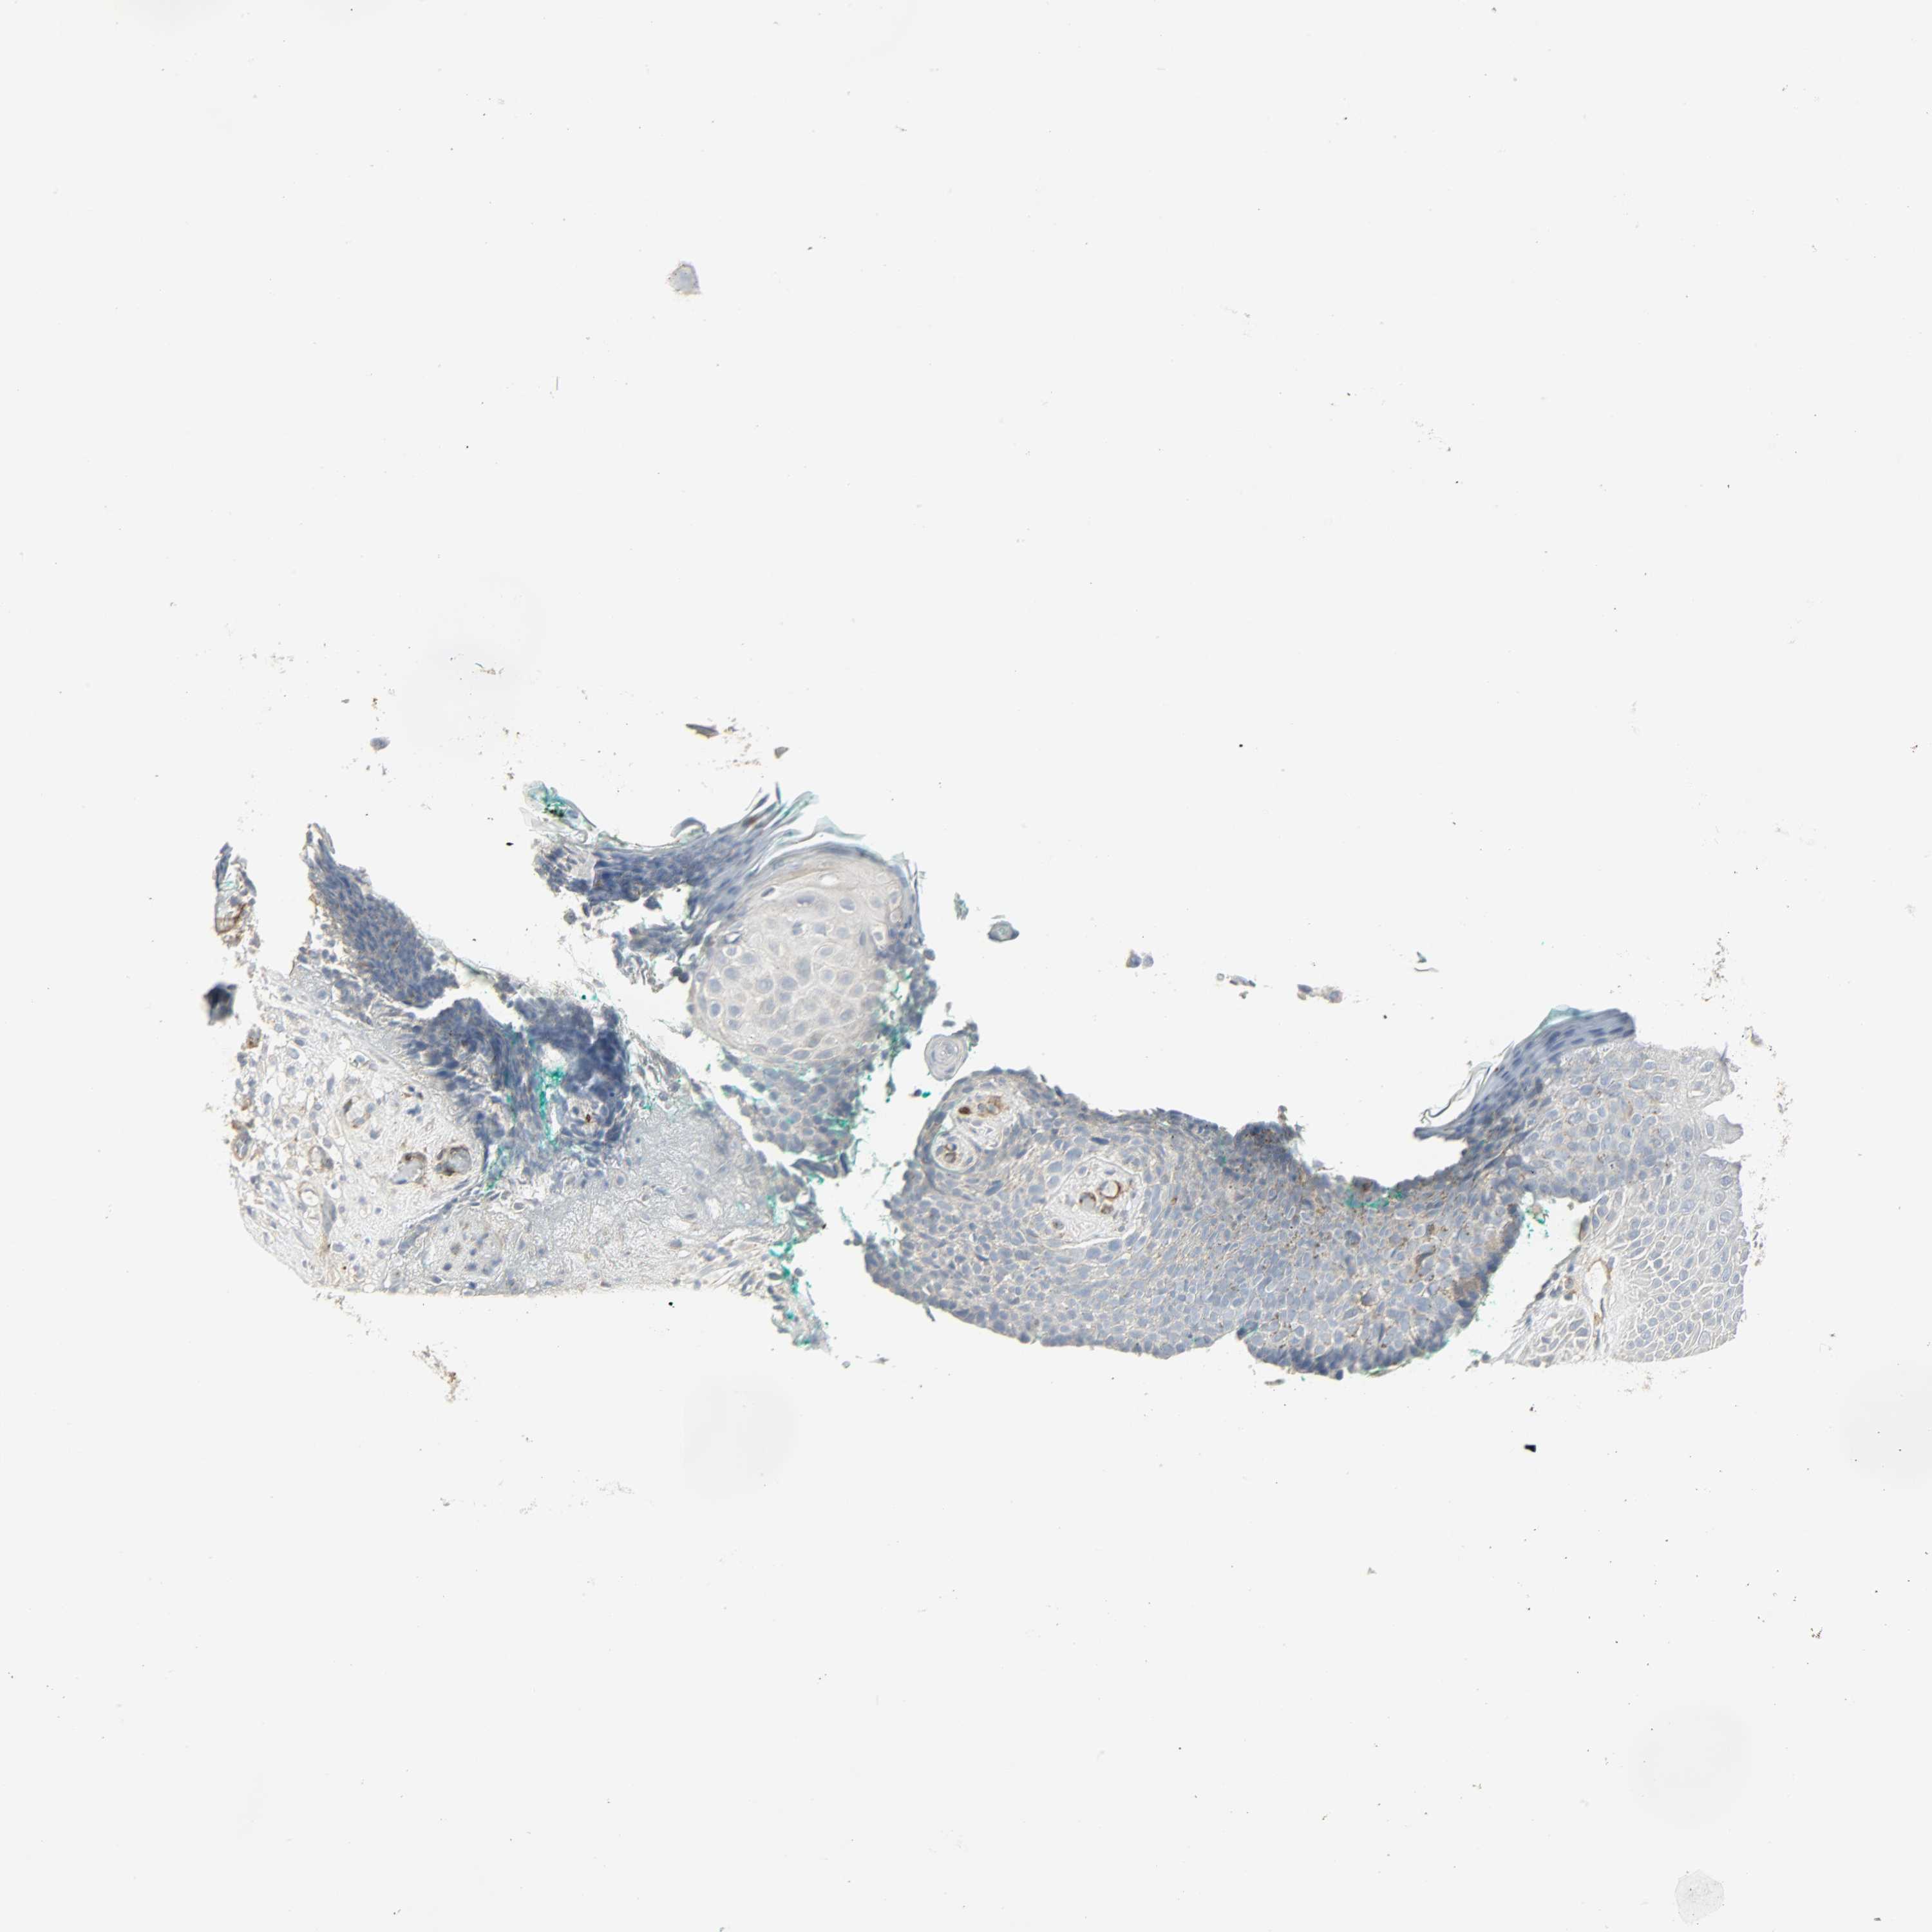

SKIN CANCER - Protein expressioni

A mouse-over function shows sample information and annotation data. Click on an image to view it in a full screen mode. Samples can be filtered based on level of antibody staining by selecting one or several of the following categories: high, medium, low and not detected. The assay and annotation is described here.

Each image is clickable and will lead to virtual microscopy that enables deeper exploration of all samples and also displays staining intensity scores, fraction scores and subcellular localization as well as patient and tissue information for each sample.

Antibody HPA005128

Squamous cell carcinoma, NOS

Basal cell carcinoma